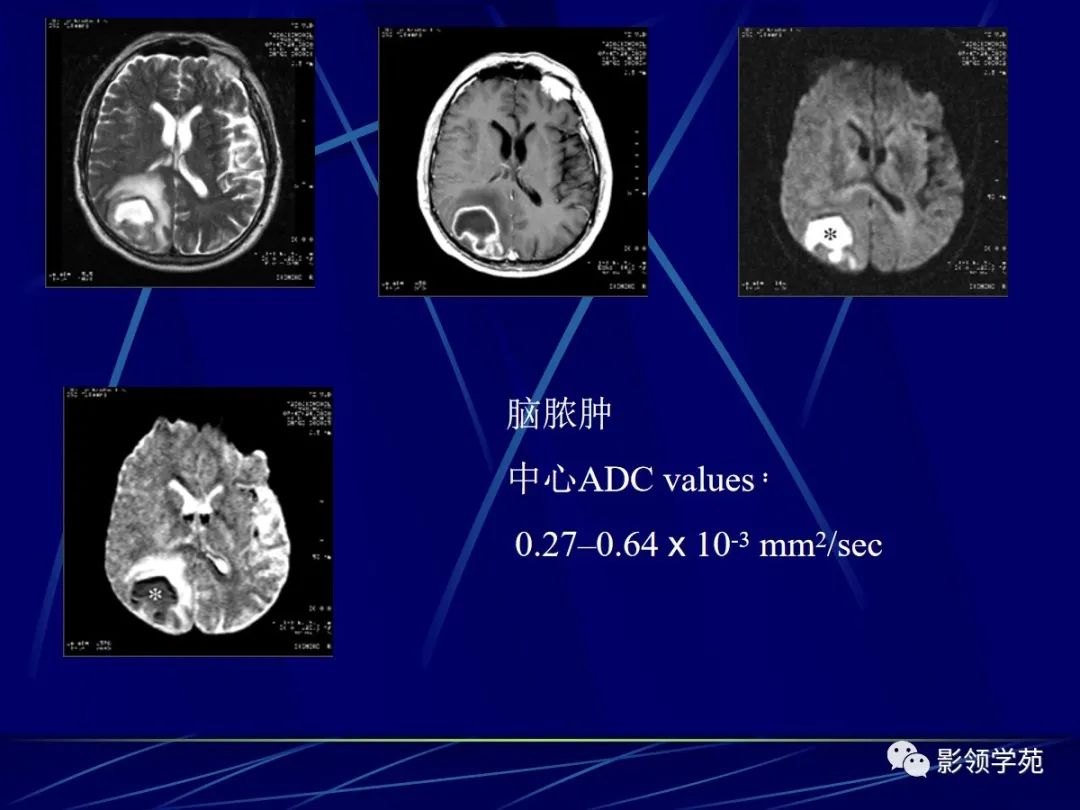

急性缺血性脑梗死与脑脓肿的鉴别诊断

• ADC 值 (据报道脑脓肿的 ADC值常常低于缺血性脑梗死的ADC值的 ±50左右)